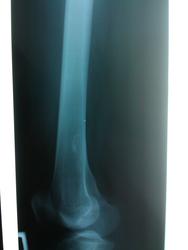

Пол пациента: Мужской пол Тип патологии: Доброкачественное новообразование, киста Область исследования: Скелетно-мышечная система Методы исследования: Rg Пациент, 27 лет. Направительный диагноз: остеома?остеобластома? правого бедра. Нужны Ваши мнения, уважаемые, доктора. https://radiomed.ru/sites/default/files/styles/case_slider_image/public/user/18609/img_20140110_145115.jpg?itok=LDrrQUNy ID:34760 Sun, 12/01/2014 - 19:59 #1 maker4ik Offline Last seen: 8 years 9 months ago Joined: 19.10.2011 - 17:49 Posts: 2682 А энхондрома не может быть? Sun, 12/01/2014 - 21:54 #2 tatyana Offline Last seen: 4 years 3 months ago Joined: 24.06.2009 - 08:33 Posts: 2090 НОФ "самоуверенность дилетантов - предмет зависти профессионалов" Sun, 12/01/2014 - 22:12 #3 Almo Offline Last seen: 4 hours 20 min ago Joined: 28.09.2008 - 18:50 Posts: 8286 Татьяна, как понимать аббревиатуру-НОФ? Sun, 12/01/2014 - 22:14 #4 Dima Offline Last seen: 7 years 4 months ago Joined: 05.08.2012 - 17:39 Posts: 2467 Almo wrote: Татьяна, как понимать аббревиатуру-НОФ? И если можно, пожалуйста, почему не остеохондрома? Терпимость - это когда прощают чужие ошибки; такт - когда не замечают их. (Артур Шницлер) Sun, 12/01/2014 - 22:43 #5 pumpan86 Offline Last seen: 10 years 1 month ago Joined: 03.01.2012 - 10:49 Posts: 60 http://www.radiologyassistant.nl/en/p494e15cbf0d8d/bone-tumor-systematic-approach-and-differential-diagnosis.html вам в помощь Sun, 12/01/2014 - 23:36 #6 tatyana Offline Last seen: 4 years 3 months ago Joined: 24.06.2009 - 08:33 Posts: 2090 неоссифицирующая фиброма или метафизарный кортикальный дефект Остеохондрома это костно-хрящевой экзостоз. Где Вы видите экзостоз? "самоуверенность дилетантов - предмет зависти профессионалов" Sun, 12/01/2014 - 23:38 #7 Dima Offline Last seen: 7 years 4 months ago Joined: 05.08.2012 - 17:39 Posts: 2467 tatyana wrote: неоссифицирующая фиброма или метафизарный кортикальный дефект Остеохондрома это костно-хрящевой экзостоз. Где Вы видите экзостоз? Прошу прощения, почему не энхондрома хотел спросить? Терпимость - это когда прощают чужие ошибки; такт - когда не замечают их. (Артур Шницлер) Sun, 12/01/2014 - 23:42 #8 tatyana Offline Last seen: 4 years 3 months ago Joined: 24.06.2009 - 08:33 Posts: 2090 отсутствие хрящевого матрикса, ободок склероза, субкортикальная локализация "самоуверенность дилетантов - предмет зависти профессионалов" Sun, 12/01/2014 - 23:45 #9 Dima Offline Last seen: 7 years 4 months ago Joined: 05.08.2012 - 17:39 Posts: 2467 tatyana wrote: отсутсвие хрящевого матрикса, ободок склероза, субкортикальная локализация Спасибо, почему-то думал что NOF должна распологаться только кортикально. Терпимость - это когда прощают чужие ошибки; такт - когда не замечают их. (Артур Шницлер) Sun, 12/01/2014 - 23:46 #10 tatyana Offline Last seen: 4 years 3 months ago Joined: 24.06.2009 - 08:33 Posts: 2090 Не в кортикале, под кортикалом http://www.radiologyassistant.nl/en/p4bc9b622f0885/bone-tumor-h-0.html#i4bc9b62301d21 http://www.bonetumor.org/tumors-bone/nonossifying-fibroma "самоуверенность дилетантов - предмет зависти профессионалов" Sun, 12/01/2014 - 23:49 #11 Dima Offline Last seen: 7 years 4 months ago Joined: 05.08.2012 - 17:39 Posts: 2467 Татьяна Валентиновна, спасибо большое за пояснения! Терпимость - это когда прощают чужие ошибки; такт - когда не замечают их. (Артур Шницлер) Mon, 13/01/2014 - 10:22 #12 Helios Offline Last seen: 9 months 2 weeks ago Joined: 06.08.2010 - 15:16 Posts: 4417 +1 за НОФ. Mon, 13/01/2014 - 10:31 #13 Катенёв Валенти... Offline Last seen: 7 years 2 months ago Joined: 22.03.2008 - 22:15 Posts: 54876 http://www.radiomed.ru/publications/onkologiya-fibroma-neossifitsirovannaya-pr-s Thu, 27/02/2014 - 01:01 #14 студент 33 Offline Last seen: 3 years 10 months ago Joined: 26.02.2014 - 23:23 Posts: 45 похожа на неоссифицирующуюся фиброму.но клиники она обычно не дает никакой....тогда это либо случайная находка,либо это не НОФ(с какой целью делали снимки)

НОФ

неоссифицирующая фиброма или метафизарный кортикальный дефект

Остеохондрома это костно-хрящевой экзостоз. Где Вы видите экзостоз?

отсутствие хрящевого матрикса, ободок склероза, субкортикальная локализация

Не в кортикале, под кортикалом

+1 за НОФ.

похожа на неоссифицирующуюся фиброму.но клиники она обычно не дает никакой....тогда это либо случайная находка,либо это не НОФ(с какой целью делали снимки)